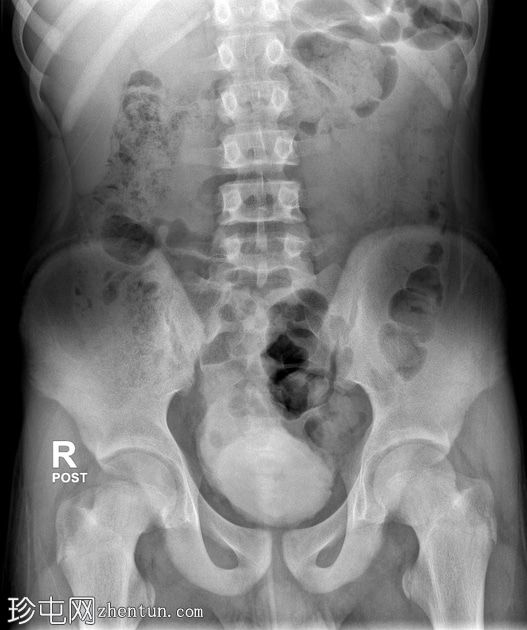

年龄:15岁

性别:男

通过导尿管注入造影剂后,可见膀胱延长,膀胱壁不规则,呈小梁状,并有多个大小不一的外囊。

排尿后序列中可见残余尿液。

本病例展示了

神经

源性膀胱的临床和放射学特征。